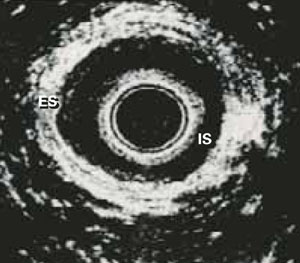

These ultrasound images show 2 discrete rings of tissue: The inner hypoechoic ring represents the internal anal sphincter and the outer hyperechoic ring represents the external anal sphincter (FIGURE 3). Disrupted continuity of these rings is consistent with structural damage to the sphincter.

FIGURE 3 Endoanal ultrasound

Disruption of continuity of the inner hypoechoic ring (IS, internal sphincter) and the outer hyperechoic ring (ES, external sphincter) on endoanal ultrasound is consistent with structural damage to the sphincter. This image shows normal anatomy.